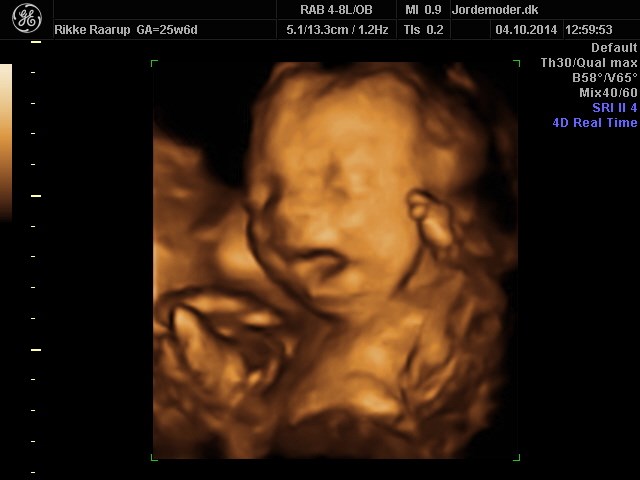

Siden har vi været til 3D/4D scanning hvor vi havde min mor og lillebrors storebror (

med. En scanning jeg var MEGET nervøs for, da vores familier stadig intet ved om at lillebror har været syg!

Scanningsdamen sagde intet om væske eller noget som helst, og lillebror vokser perfekt. Så det var enormt lettende. Han følger alle kurver rigtig flot og sparker derud ad!

Vedhæftede fotos (klik for at se i fuld størrelse)